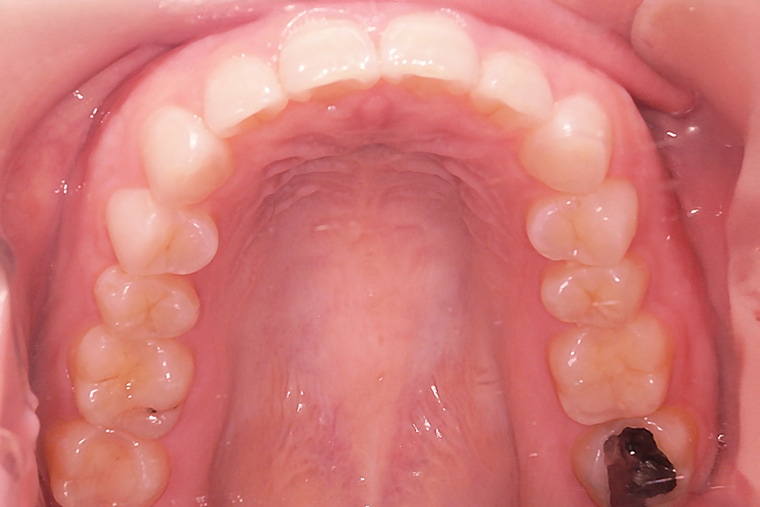

AFTER